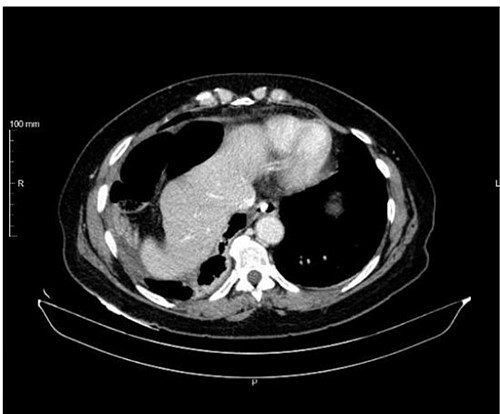

An abdominal computed tomography (CT) scan was performed, which identified an internal hernia at the root of the right mesentery, an apparent abscess in the right lung base (65 × 55 mm) (Fig. 1) as well as elevation of the right diaphragmatic hemi-dome with Chilaiditi sign (Fig. 2).

The patient underwent exploratory laparotomy, and there was a right diaphragmatic hernia with an intestinal loop in the chest. The hernia orifice was enlarged and the jejunal loop was reduced, which was necrotic without perforation (Fig. 3). Segmental enterectomy with later-lateral anastomosis was performed and a diaphragmatic repair was done with non-resorbable suture thread (Fig. 4). The abdominal and the right pleural cavities were washed and a chest tube was placed in the fifth intercostal space.